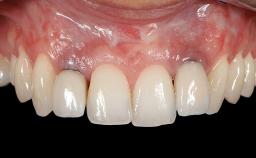

Implant Placement in the Esthetic Zone and Coverage of Multiple Gingival Recessions

This case illustrates use of a modified ‘tunnel’ technique, which has been shown to be highly effective in root coverage procedures. The tunnel technique is used to achieve soft-tissue augmentation across the anterior area, including the planned implant site, using collagen matrix as grafting material. The patient is a 47-year-old woman with high esthetic expectations. Her main concern was the appearance of the anterior teeth and their “elongation”.